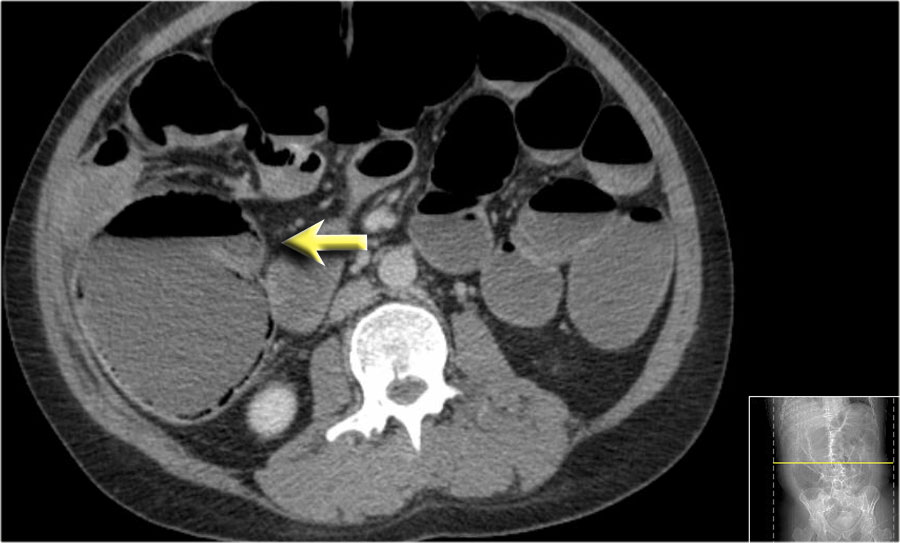

Các hình ảnh này thuộc về bệnh nhân bị tắc ruột non dạng quai kín.

Lưu ý nhóm các quai ruột non có thành dày ở vùng bụng trên phải (mũi tên vàng).

Phù nề mạc treo ruột (mũi tên đỏ) cho thấy tình trạng tăng áp lực tĩnh mạch do thắt nghẹt.

Giãn mạch máu

Tăng áp lực tĩnh mạch trong thắt nghẹt cũng dẫn đến giãn tĩnh mạch (mũi tên vàng).

Bệnh nhân này cũng có tắc ruột dạng quai kín với kiểu ngấm thuốc xám của các quai ruột bị thắt nghẹt (mũi tên đỏ).

Lưu ý sự ngấm thuốc bình thường của ruột non ở phía trên vị trí tắc nghẽn (mũi tên xanh lá).